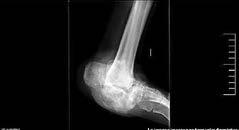

ARTROPATÍA DE CHARCOT. ................................................................................98

Alba Edo Olucha.

Cirugía Ortopédica y Traumatología.

Hospital Universitario de Navarra (HUN)

Supervisión clínica: D’Arrigo Azzarelli A.F.